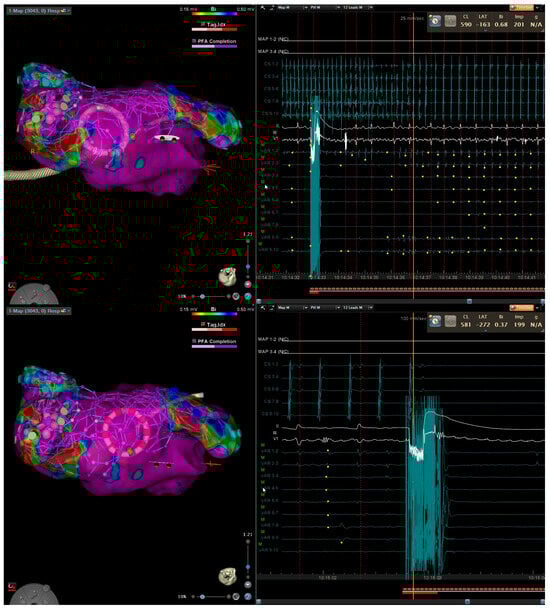

Figure 3.

Three-dimensional electroanatomical mapping of left atrium (left) and EGM (right) (top) and entrainment mapping (bottom) using the VARIPULSE catheter in a patient with atypical atrial flutter after two previous ablations. The isthmus of flutter was located at posterior wall close to the antrum of left inferior pulmonary vein based on entrainment (bottom) and activation map (top). Application at this site terminated the atrial flutter.